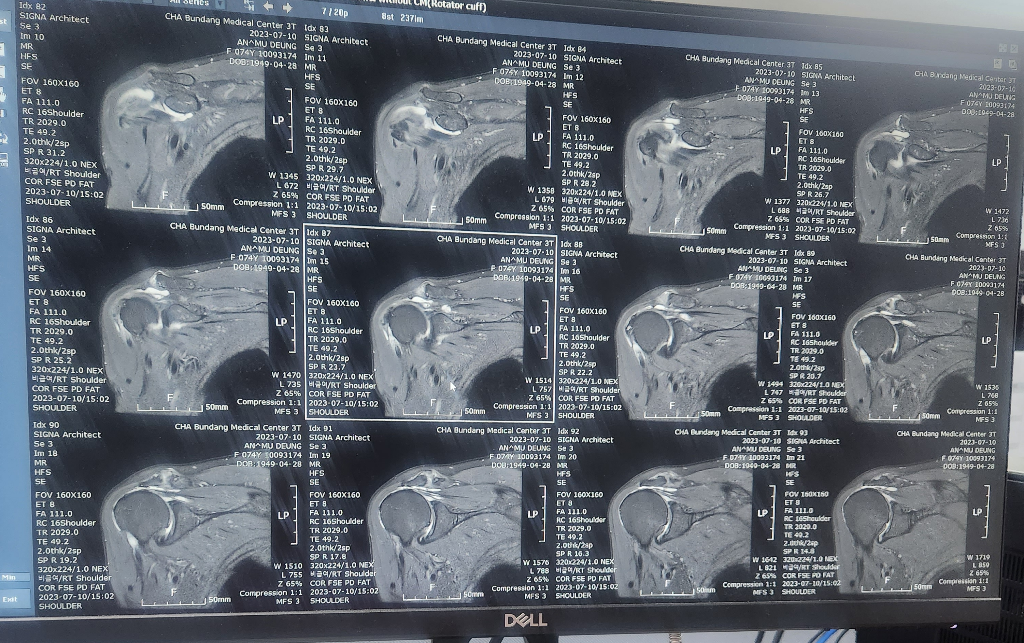

할머니가 넘어지면서 어깨를 다쳤는데

검사만하고 설명은 다음으로 미뤄져서요..

혹시 이 영상만으로 현재 어깨상태 문의드려도될까요

현재 어깨관절에 물이 차있는 소견으로 염증이 있는 것으로 보이며, 회전근개의 경우는 영상의 크기가 작아 정확한 판단은 어렵겠습니다.